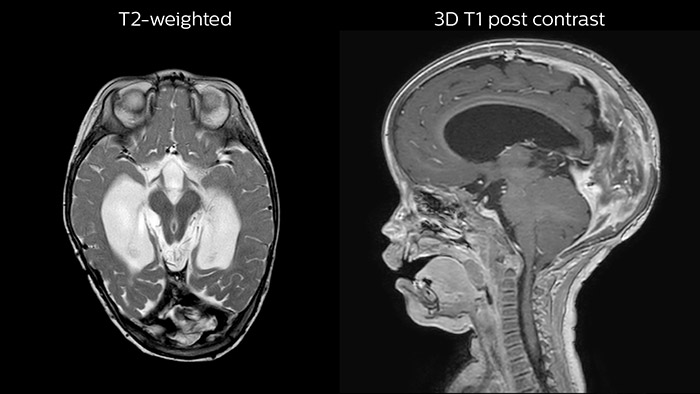

Leukodystrophy in a teenager

Rostral meningitis and arachnoiditis Both images are from the same 3D T1-weighted post contrast sequence in a newborn, under treatment.

Since scan times of 3D scans can be significantly shortened thanks to Compressed SENSE, the MRI team is performing more 3D scans than before. “The advantage of 3D scanning is that we capture one high resolution sequence, but we can reconstruct images in any orientation, even after the scan, when looking at the images for diagnosis. Having this ability to view any crosssection we need in high resolution, can make re-scanning unnecessary,” says Dr Junge. “We are currently optimizing our routine head examination to include more 3D scans, including T1- weighted, T2-weighted and FLAIR.”

Hydrocephalus post hemorrhagic Both pictures show a ventriculoperitoneal shunt. With our previous scanner our hydrocephalus protocol needed about 25 min. With Ambition the examination time is about 14 min. including a CSF PCA sequence to show flow in the aqueduct.